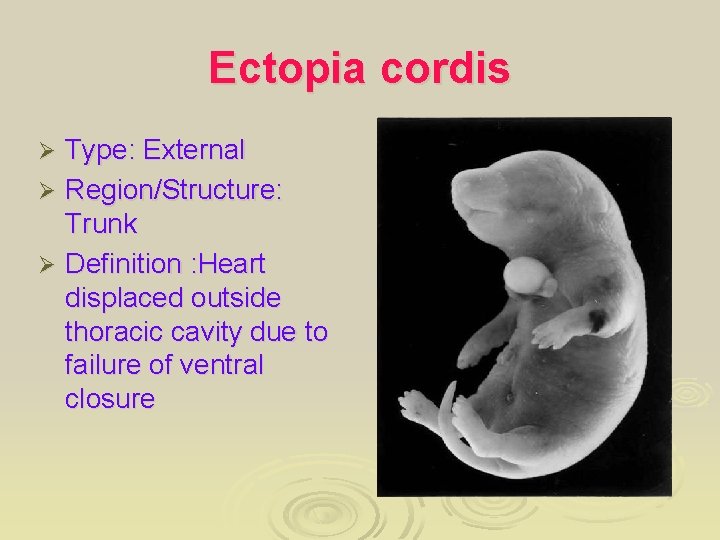

Ectopia cordis Type: External Ø Region/Structure: Trunk Ø Definition : Heart displaced outside thoracic cavity due to failure of ventral closure Ø